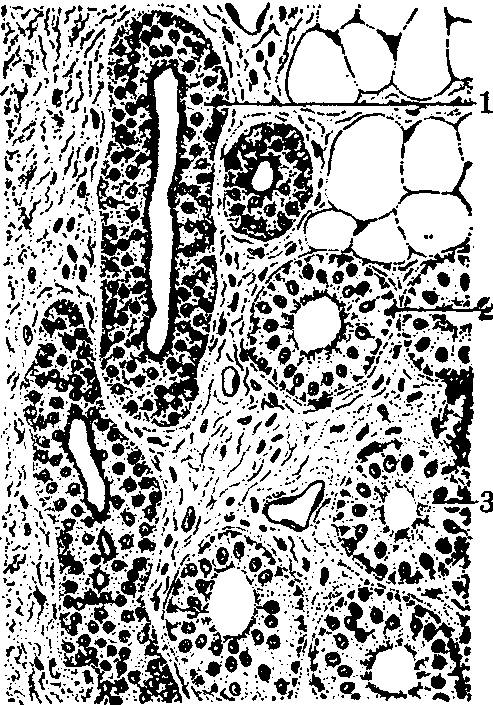

外泌汗腺的结构(高倍光镜)

1.导管 2.分泌部的肌上皮细胞 3.分泌部

分泌部周围有厚并显透明的基膜。腺细胞为一层,呈锥体形、立方形或柱状(见图)。普通染色标本中能见两型腺细胞:明细胞较大,顶部窄,底部宽,胞质显嗜酸性;暗细胞较小,夹在明细胞之间,顶部宽,底部窄,胞质显嗜碱性。在腺细胞基底面与基膜间有梭形、有突起的肌上皮细胞,核扁长,胞质易被伊红染红色,含许多肌原纤维,其性质与平滑肌细胞的相似。电镜下,暗细胞内高尔基复合体明显,有许多游离核糖体,粗面内质网和分泌颗粒。分泌颗粒含粘蛋白。明细胞有丰富的滑面内质网,粗面内质网和游离核糖体少,糖原颗粒多。细胞基底面的胞膜形成形状复杂的内褶。相邻腺细胞间有细胞间分泌小管,可能由此处分泌水和离子。分泌部突然变细成为导管。导管腔小,管壁常为二层立方形细胞,胞质显强嗜碱性,周围有基膜(见图)。深层细胞附着于基膜,核较大,线粒体较多。浅层细胞位于近腔面,细胞较小,核大而不规则,胞质较少。胞质近游离面有密集的细丝交织成网,于普通染色切片上,见细胞游离面有一层较厚的嗜酸性物质,称小皮,即相当于此网。导管没有肌上皮细胞。表皮内导管由3~4层较扁的细胞围成,胞核已不清楚,胞质含透明角质颗粒。此腺分泌清明的低渗液,即汗,它含大量水分,并含钠、钾、氯、乳酸和尿素,有少量蛋白。导管能吸收钠和氯。汗是腺细胞的分泌产物,不是血浆的滤液。全身的腺不同时分泌。环境温度高时,前额和鼻部先分泌,其后是面部、躯干和四肢,最后是手掌和足蹠。受精神和情感刺激时,手掌和足蹠先分泌,其它部分后分泌。汗腺主要在环境温度高时分泌,但也受体内代谢活动和疾病的影响。汗腺分泌物蒸发,促使人体散热,并排出一些代谢产物。汗的排出量和成分随环境温度和身体代谢状况而变化。汗腺分泌平时主要受胆碱能神经的调节。肾上腺素能纤维主要在应激状态下起调节作用。